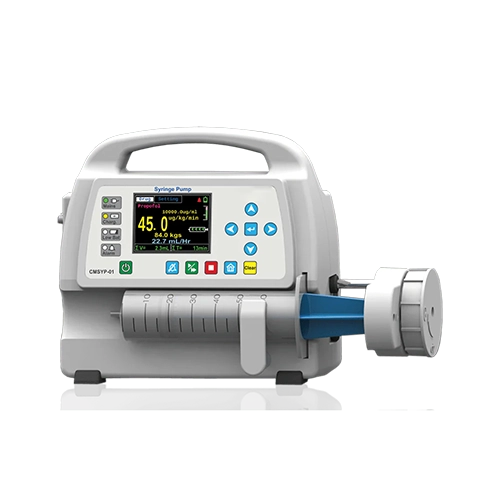

Alxa Medical Technology LLP is a specialized Bubble CPAP Machine Manufacturers in Noida, focused on delivering end-to-end neonatal and critical care medical equipment for modern healthcare facilities. Our comprehensive product range includes Nasal Prongs and Nasal Masks for safe oxygen delivery, advanced Ventilators for controlled respiratory support, and precision-based Syringe Pumps and Infusion Pumps for accurate medication and fluid administration. Each device is designed to meet the critical demands of NICUs and ICUs, ensuring reliability, ease of use, and consistent performance. By combining innovative engineering with medical-grade materials, we manufacture equipment that supports effective clinical decision-making and improved patient care.

As established Ventilator Suppliers in Uttar Pradesh, Alxa Medical Technology LLP provides healthcare institutions with a complete ecosystem of respiratory and infusion solutions. From initial oxygen therapy using Nasal Prongs and Nasal Masks, to advanced mechanical ventilation with Ventilators, and controlled infusion through Syringe Pumps and Infusion Pumps, our products are designed to function together seamlessly. We prioritize timely supply, quality assurance, and dependable service support, enabling hospitals to maintain uninterrupted critical care operations. Our solutions are trusted for their compatibility, durability, and adaptability in high-pressure clinical environments.